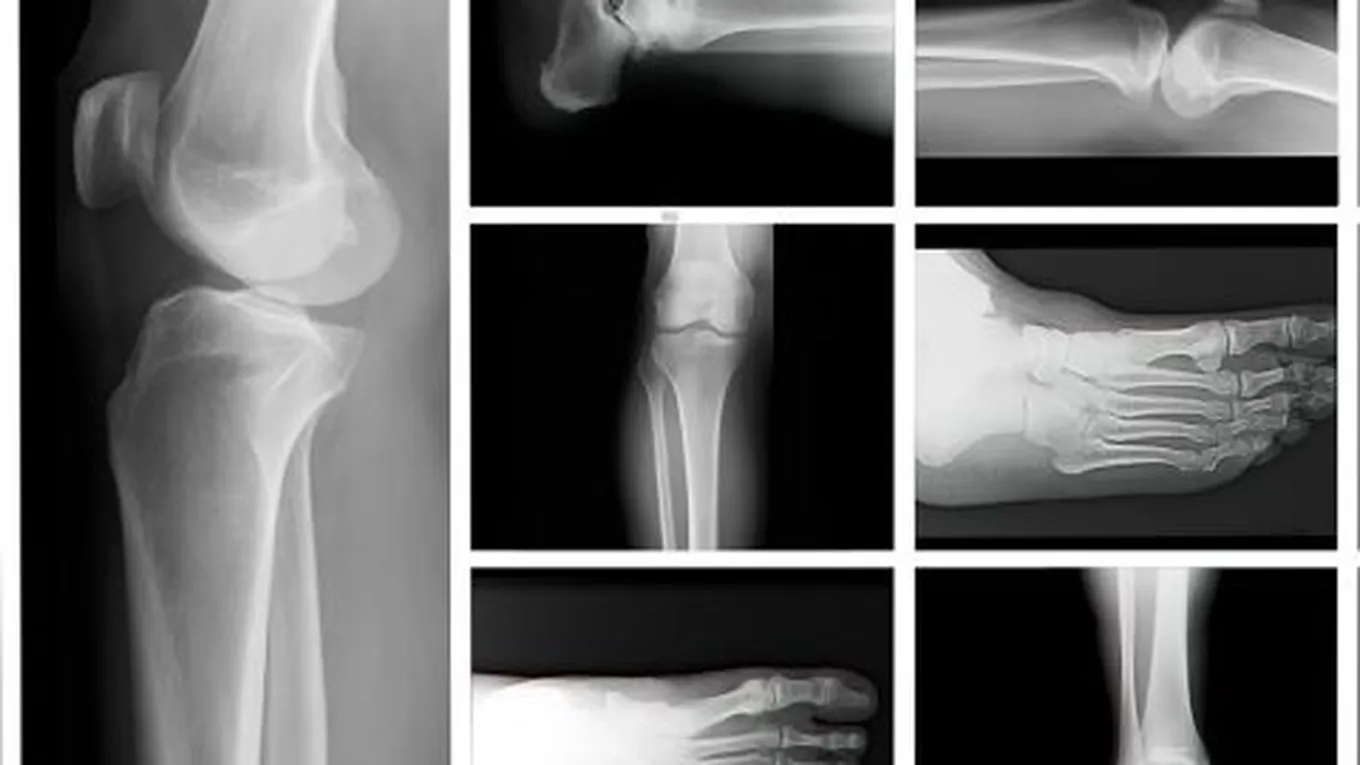

توجد في العظام في الوضع الطبيعي مسافات صغيرة، وعند زيادة حجم هذه المسافات عن الحدّ الطبيعيّ تقل قوة العظام وكثافتها، ويصبح الجزء الخارجي من العظام أضعف وأقل سمكاً، وهذا ما يُعرف ببساطة بمرض هشاشة العظام (بالإنجليزية: Osteoporosis)، ويُعدّ هذا المرض الذي يُصيب العظام من الأمراض الشائعة، إذ قُدّر عدد المصابين به في الولايت المتحدة الأمريكية والذين ترتفع احتمالية إصابتهم به بما يُقارب 53 مليوناً، وعلى الرغم من أنّ مرض هشاشة العظام قد يُصيب الأفراد بغض النظر عن أعمارهم، إلا أنّه غالباً ما يؤثر في الأسخاص الكبار في السنّ وخاصة النساء، ومن الجدير بالذكر أنّ مرض هشاشة العظام يتسبّب بمعاناة المصاب من كسور العظام، إذ تكون العظام أكثر عُرضة للكسور حتى خلال ممارسة الأنشطة اليومية مثل الوقوف والمشي، وتجدر الإشارة إلى أنّ عظام المعصم، والعمود الفقري، والورك، والقفص الصدريّ الأكثر شيوعاً للإصابة بالكسور في الأشخاص الذين يُعانون من هشاشة العظام.[1]